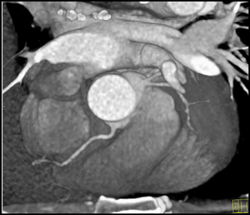

Plaque in RCA